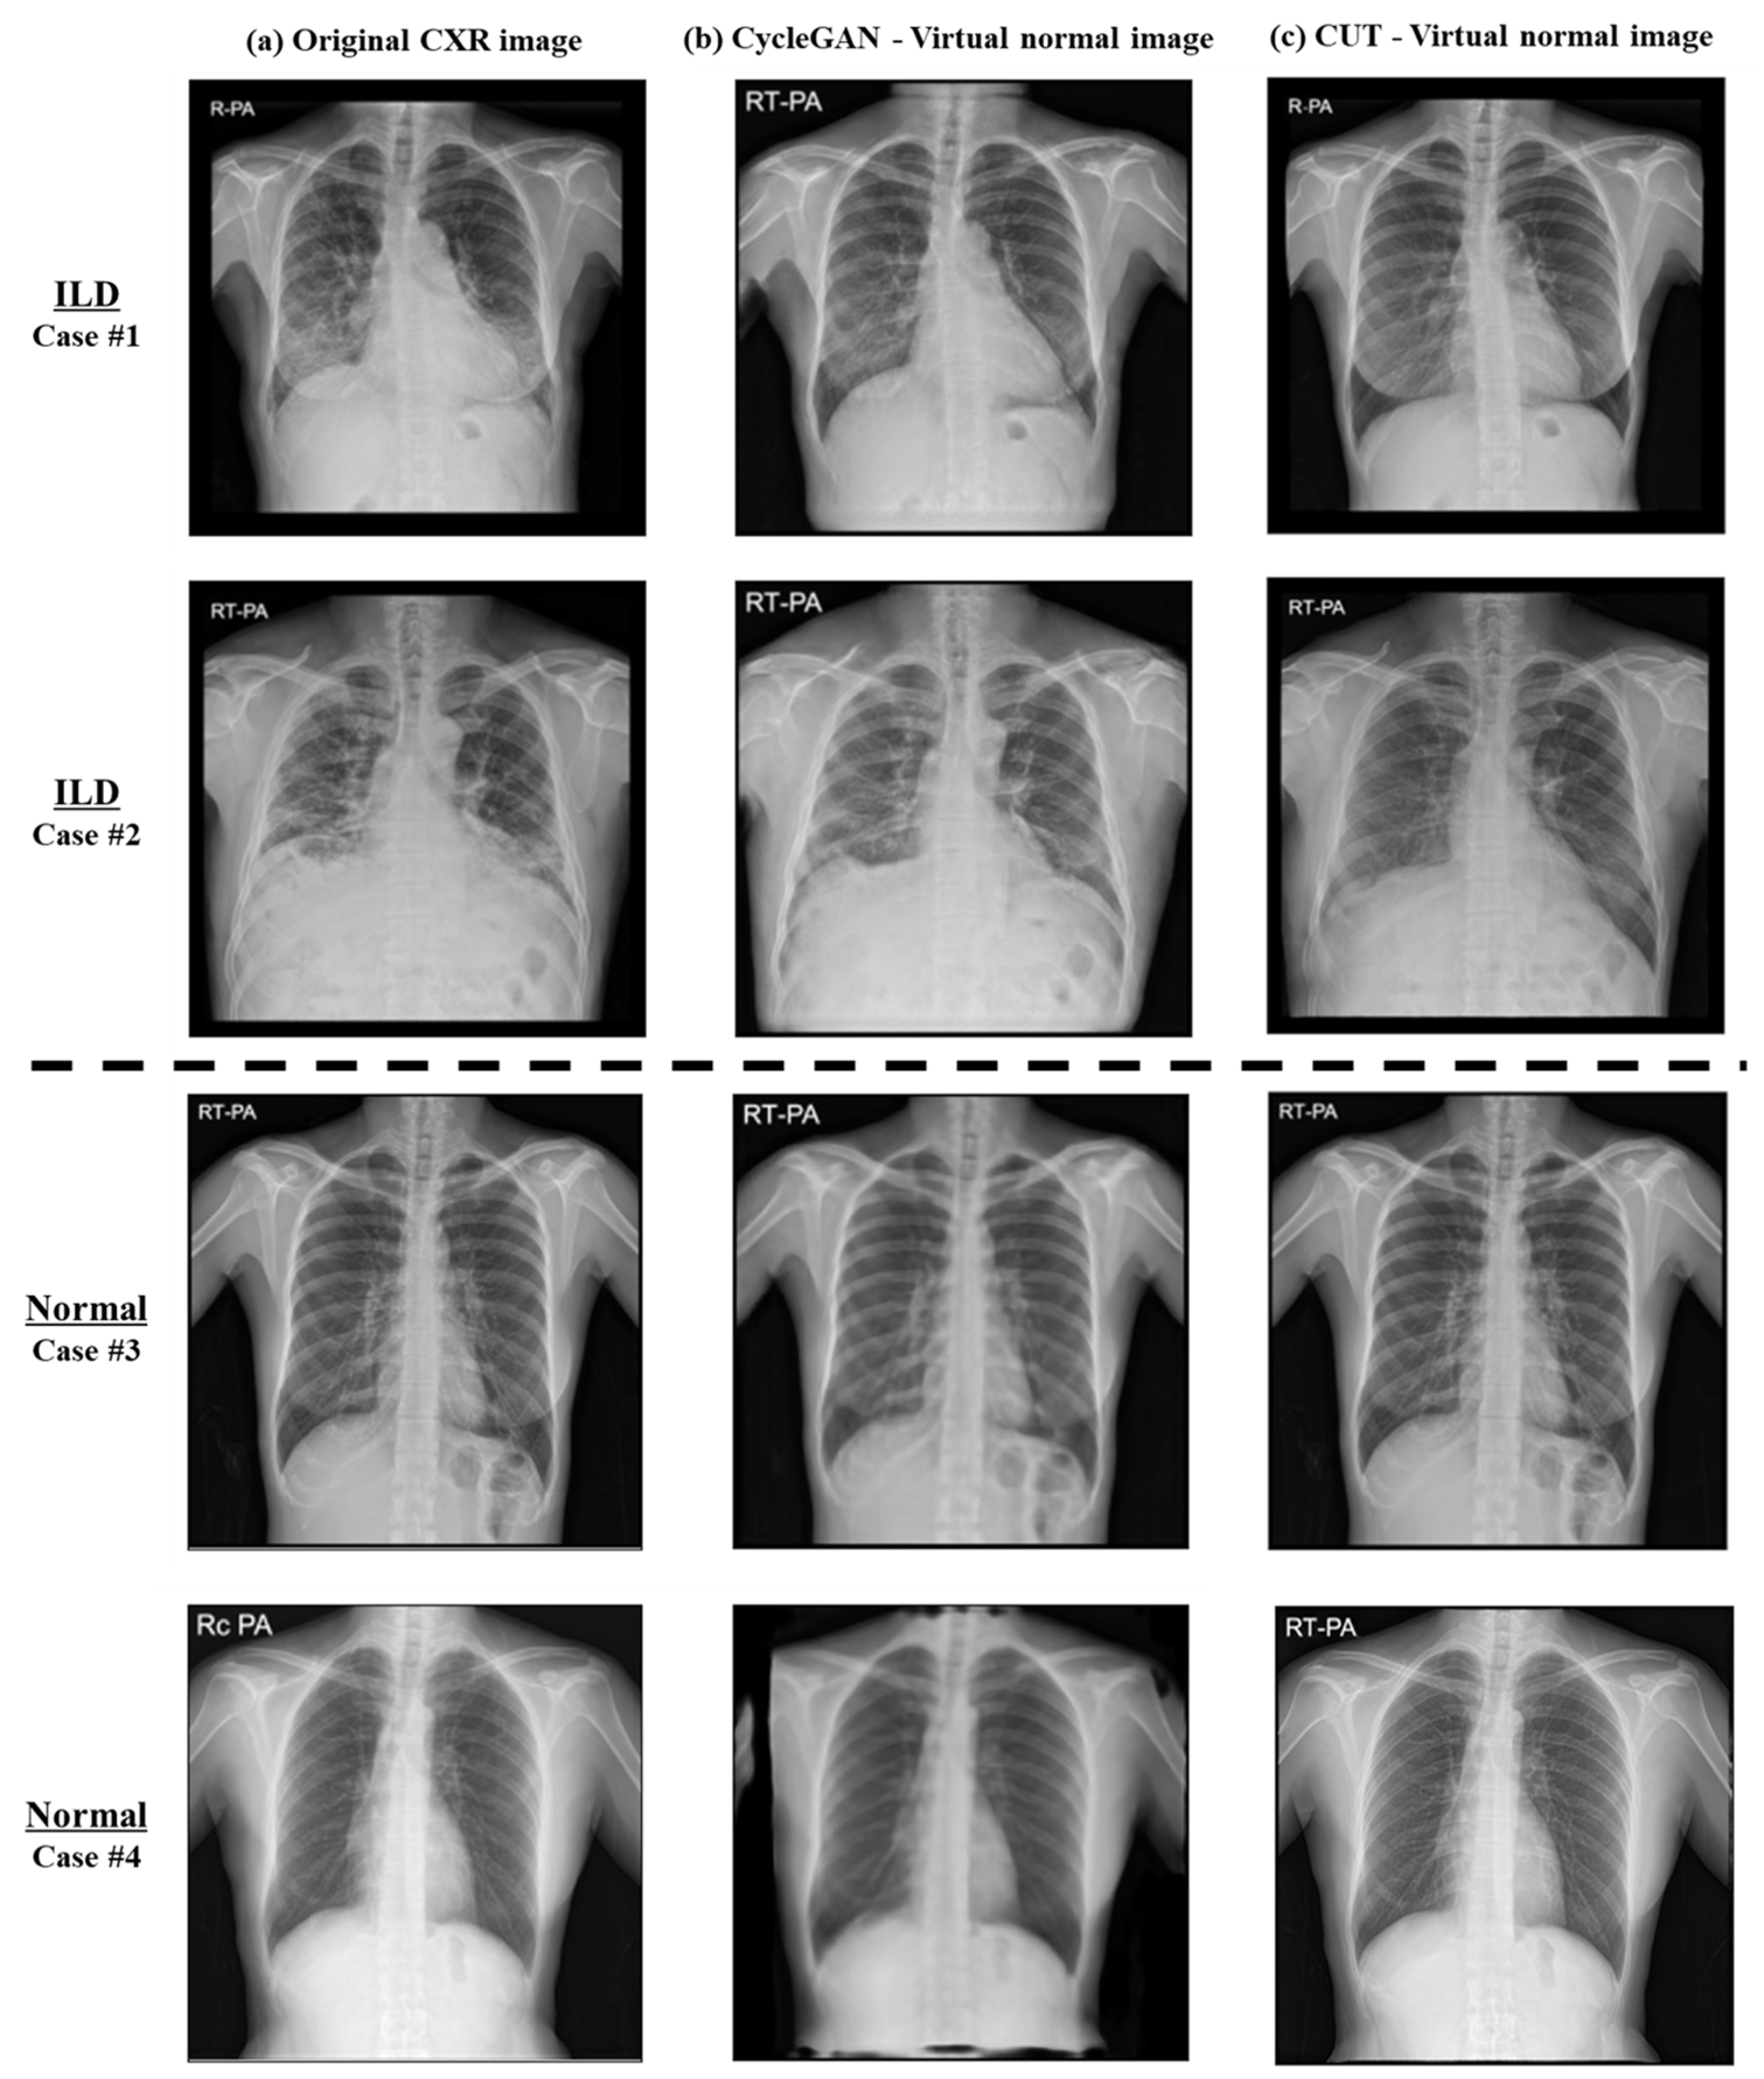

| Model | CycleGAN | CUT | |||

|---|---|---|---|---|---|

| Evaluation metrics | SSIM | PSNR | SSIM | PSNR | |

| Category of dataset | Normal | 0.88 | 23.68 | 0.97 | 36.43 |

| ILD | 0.71 | 18.46 | 0.90 | 26.61 | |